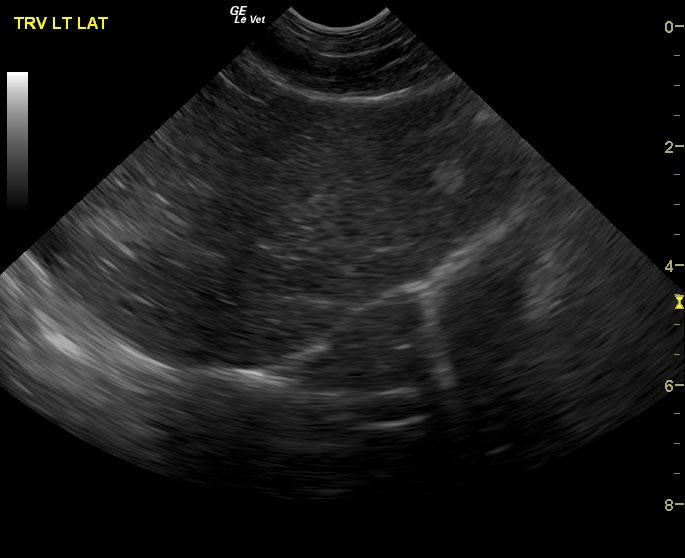

A 16-year-old neutered male DSH cat with a history of weight loss and inflammatory bowel disease was presented for poor appetite. Dehydration, dental disease, and nasal discharge were noted on physical examination. Hematuria was present on urinalysis. Initial CBC showed leukocytosis and anemia, which remained fairly unchanged after a month of antibiotic therapy.